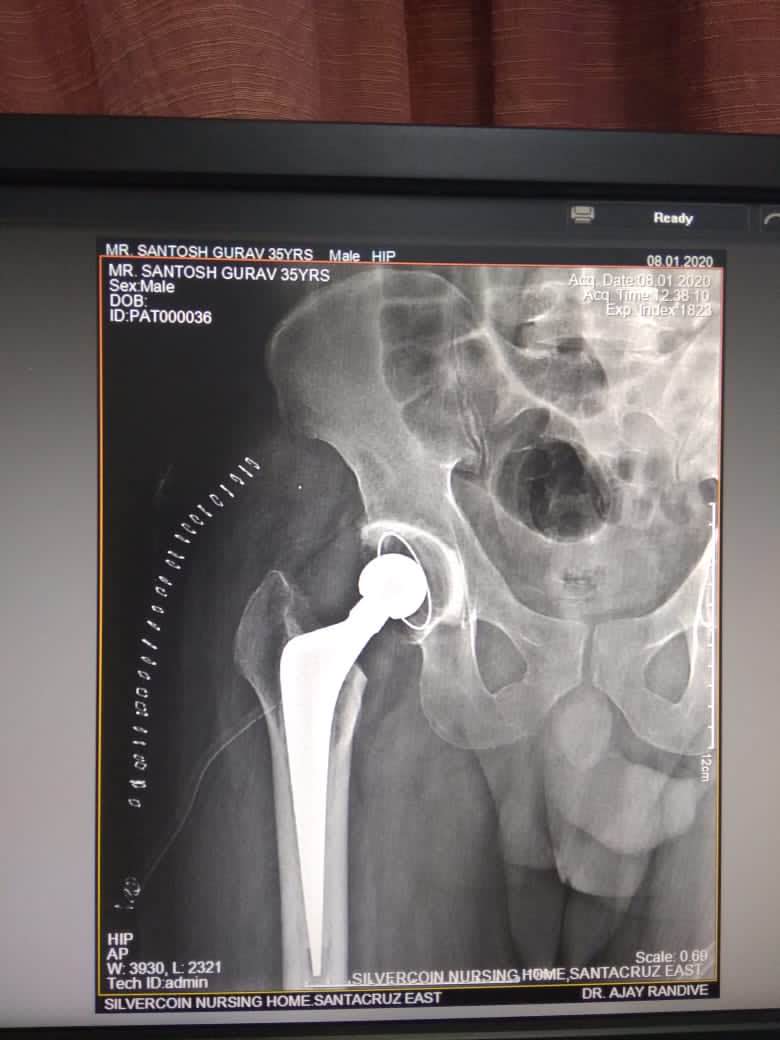

Best HIP SURGEON IN ANDHERI AND SANTACRUZ